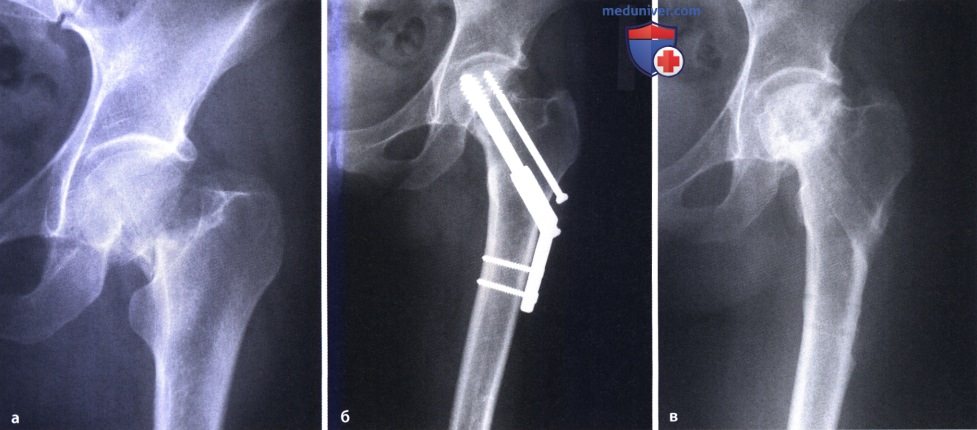

Некроз тазобедренного сустава: Фотографии и особенности лечения

Раздел: Необычные решения